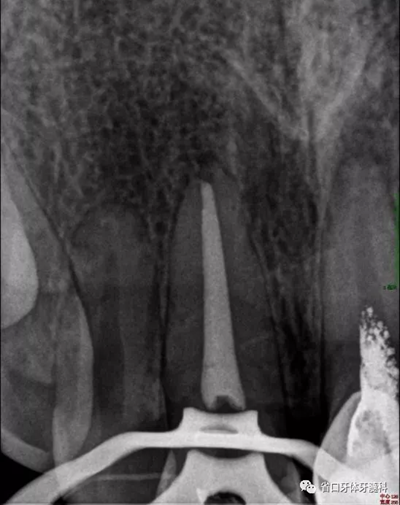

2周后復(fù)診:封藥存,患牙無不適,叩痛-,齦無紅腫。去封藥,清理根管,試主尖到位,沖洗、干燥,熱牙膠充填至釉牙骨質(zhì)界下2mm,照片顯示恰充。

圖5 根充片